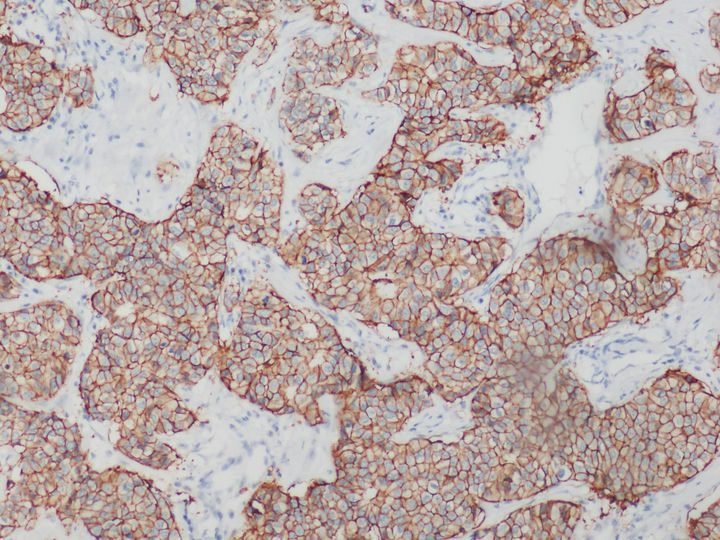

HER是一類與細(xì)胞增殖息息相關(guān)的蛋白質(zhì),全稱是human epidermal growth factor receptor,中文叫作人表皮生長(zhǎng)因子受體。HER蛋白質(zhì)家族共有四兄弟,其中HER2負(fù)責(zé)將細(xì)胞膜外的生命信息傳導(dǎo)至細(xì)胞內(nèi),是乳腺癌診斷指標(biāo)之一,檢測(cè)HER2一般用正置熒光顯微鏡,使用免疫組化或熒光原位雜交FISH技術(shù)。

在乳腺癌,胃癌等腫瘤篩查領(lǐng)域中,HER2的表達(dá)水平是腫瘤檢測(cè)的常用指標(biāo)。目前,HER2基因檢測(cè)常見(jiàn)方式以免疫組化IHC技術(shù)和FISH技術(shù)為主。

免疫組化HER2檢測(cè)可以用普通顯微鏡明場(chǎng)觀察實(shí)現(xiàn),設(shè)備要求較低,但靈敏度和特異性相對(duì)弱。